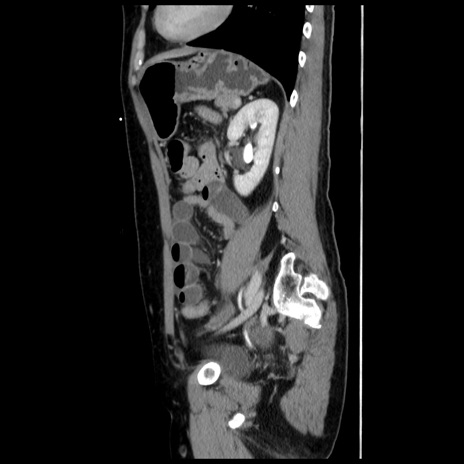

症例10(矢状断像)

【症例】 50歳代女性

【主訴】 腹痛

【現病歴】前日生レバーを食べた。今朝に排便あり。 昼前に突然発症の腹痛を生じ、当院救急外来を受診した。

【既往歴】 子宮筋腫にてで子宮全摘後

【身体所見】 意識清明、腹部:平坦、軟、下腹部やや左を中心に圧痛・反跳痛あり、筋性防御あり

【データ】WBC 7800、CRP 0.07